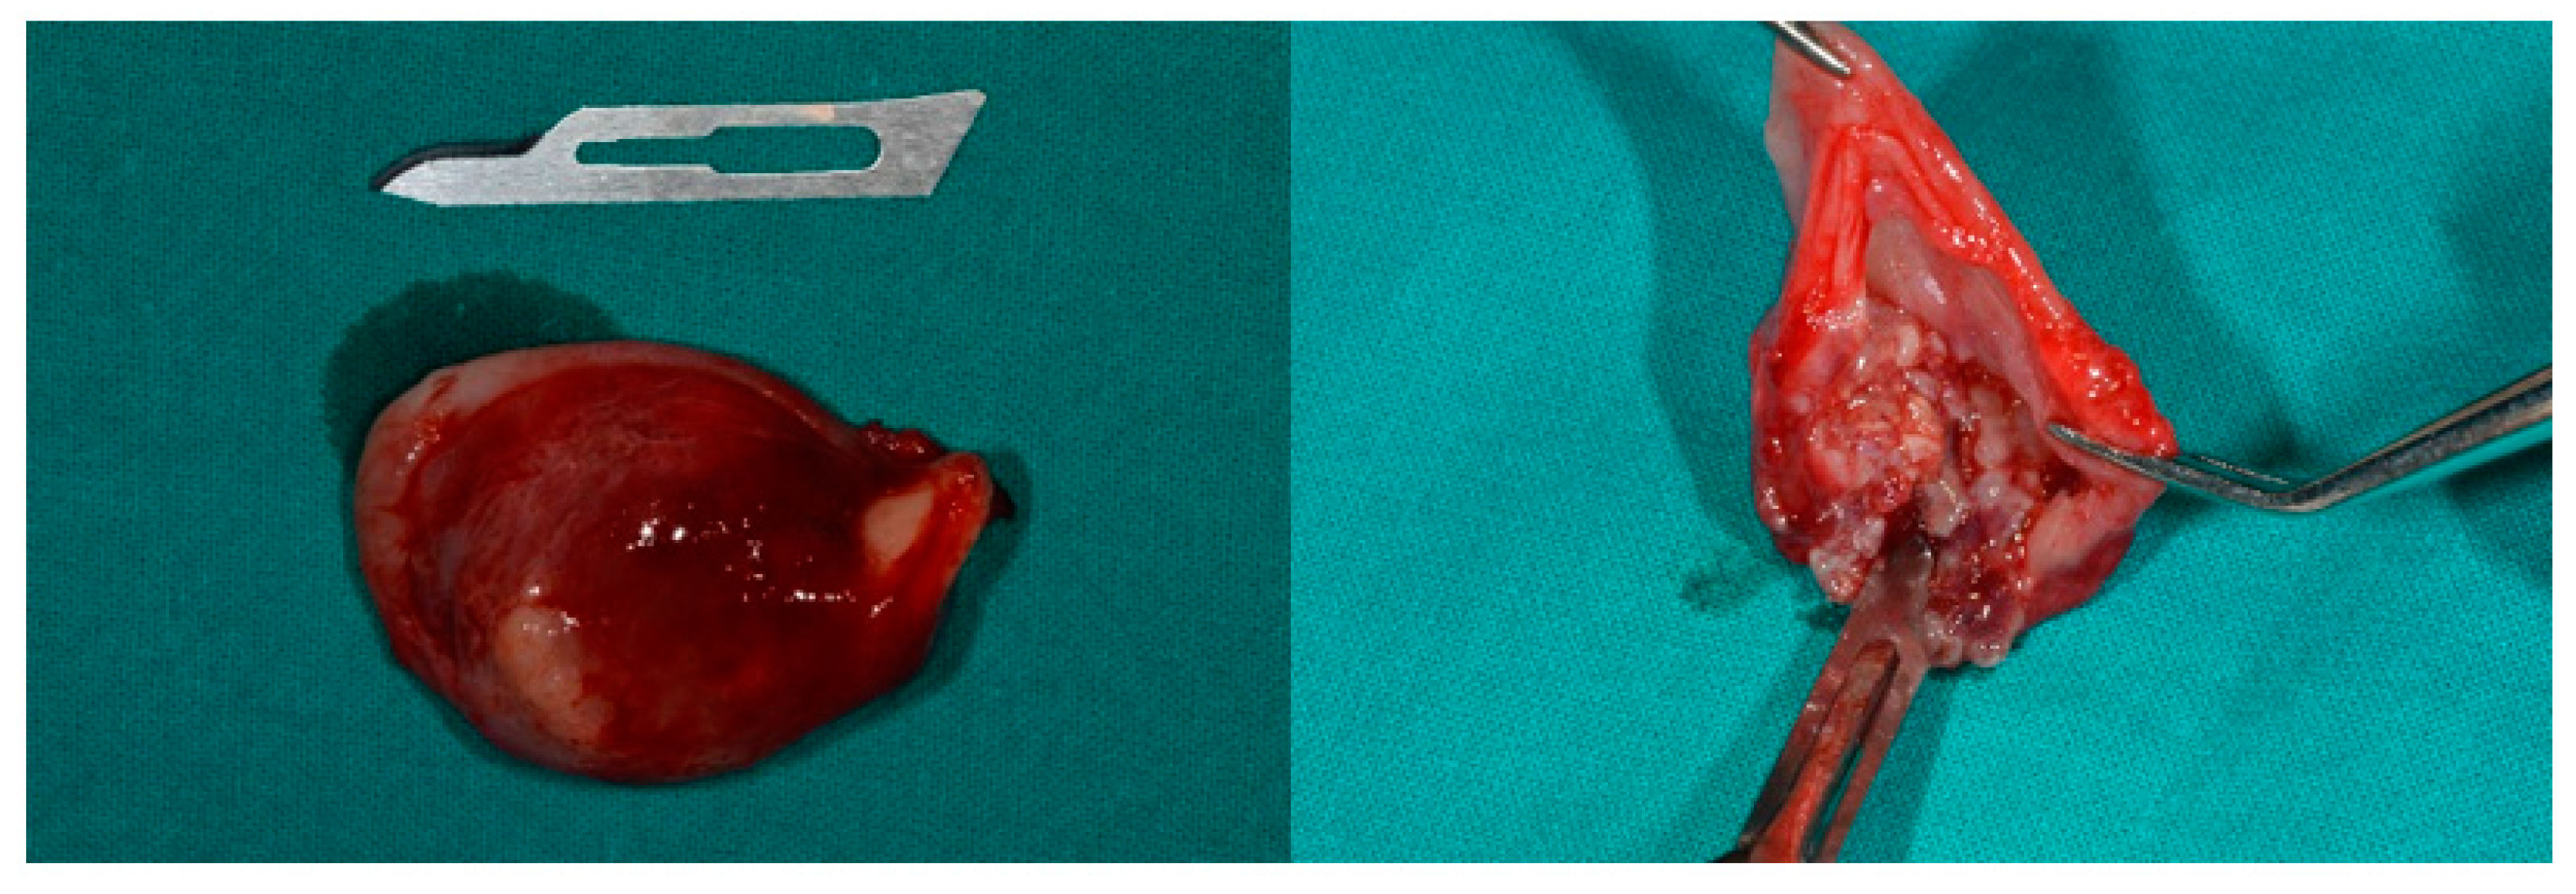

The treatment plan included the cystectomy and the surgical extraction of the impacted canine with the elevation of a full-thickness flap. The surgery was scheduled for local anesthesia. The complications of the surgery included communication with the maxillary sinus. Routine preoperative laboratory tests including a full blood count, blood clotting tests, azotemia, glycemia and creatinine levels were conducted. Additionally, a cardiologic evaluation, including an electrocardiogram, was performed. The patient was briefed on the potential risks and benefits associated with the surgical procedure. Informed consent was obtained, and the surgery was scheduled accordingly. After local anesthesia with three carpules of articaine hydrochloride + adrenaline 1:100,000, a full-thickness flap with a mesial release incision to the lateral incisor and distal to the first molar was performed by using a Bard–Parker #15 scalped blade. The flap was raised and held in place using a Langenbeck retractor (Figure 3), and the lesion was completely enucleated along with the impacted right maxillary canine (Figure 4). The permanent canine was entirely within the lesion. The tooth and lesion were removed together. Figure 5 shows the clinical aspect of the lesion. The lesion was entirely benign and encapsulated which allowed the roots of the involved dental elements (1.2, 5.3, 1.4, 1.5, 1.6) to be easily isolated during the enucleation. Saline solution rinses and closure with Vicryl 3.0 sutures were performed.

Histological examination showed a cystic lesion with a fibroconnectival wall lined by odontogenic epithelium. The lumen was occupied by a solid multinodular epithelial proliferation composed of medium-sized pale cells, with focal whorled arrangement, alternating with cribriform areas represented by small cuboidal cells. In this context, single-layered columnar cells with tubular structures, duct-like and with a pseudo-rosettes pattern were observed. Hemorrhage and small calcification were also detected. Necrosis and significant cytoarchitectural atipia were absent (Figure 7 and Figure 8).

Figure 5. Clinical aspects of the lesion and crown of tooth.